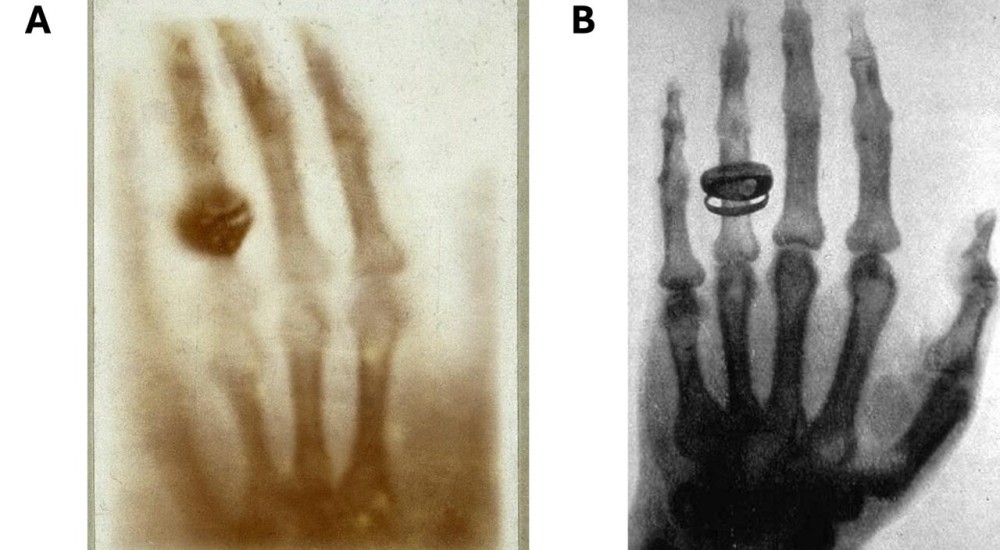

Los dedos de un gato

Por: Dr. David René Romero Camarena

Visto: 3377 veces

hace 8 meses

¿Cuántos dedos tiene un gato? Sí, aquellos que somos aficionados a estos animales hemos experimentado el afecto que pueden expresar...

Leer más